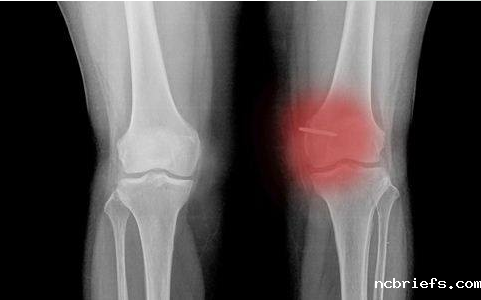

【摘要】:骨密度低不仅是老年人的专利,现在越来越多的年轻人也易骨密度低从而患上骨质疏松的症状,骨密度检测仪厂家小编提醒现在年轻人对于自身的骨密度检查不容忽视。那么骨密度低都有哪些症状呢,下面骨密度检测仪厂家小编给大家具体介绍下!

2、骨密度低的人常常在睡醒的时候或是是低头的那时候会觉得到肘关节部位不适感,乃至在用劲干咳的那时候满身的关节都会有涨痛的感觉。有某些长期骨密度低的人身椎体骨小梁会发生萎缩,并且锥体会渐渐地被缩小变形。